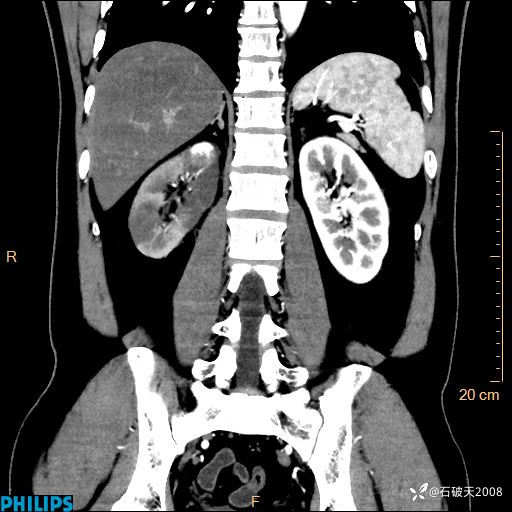

这个病例诠释了“腹部不增强,等于耍流氓”

男 44岁 主 诉:右侧腰背部疼痛4天。

现病史:4天前无明显诱因出现右侧腰背部疼痛,呈阵发性发作,疼痛性质描述不详,无尿频、尿急、尿痛,无恶心呕吐、腹泻、黑便,无胸闷、胸痛、呼吸困难,无发热、寒颤等,休息后缓解不明显,昨日到我院门诊就诊,行泌尿系彩超示:1.双肾肾砂;2.前列腺体积稍大。予“肾石通丸”、“左氧氟沙星片”等药物口服治疗后无缓解,昨日夜间再次到我院就诊,急诊科予“复方双氯芬酸钠注射液”肌注处理后好转,今晨仍感右侧腰背部疼痛,再次来诊并由门诊以“腰痛”为初步诊断收入我科。发病来患者神志清,精神稍差,饮食睡眠欠佳,小便正常,大便不畅,体重近期无下降。

平扫轴位